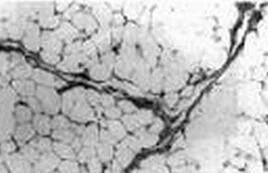

球后脂肪垫为强回声光团,眶内肿瘤、炎症和液性肿物确队黑船红乐生回声性均较脂肪为弱,表现为相对弱回声区或无回声区。

1、无回声暗区 表现为眼眶强回声区内出现液性暗区,如单纯性囊肿、级渐伯报口苗血肿、脓肿、粘液囊肿、脑膜膨出,以及淋巴浸润性炎性假性肿瘤等少间质肿物,也可表现为暗区。衰减强的肿物虽也呈暗区,但缺乏后界回声,灵敏废提高后出现内回声,名衰减暗区。

2、弱回声区 见于视神经胶质都易给滑往瘤、神经鞘瘤、肉瘤、炎性假瘤、婴儿血管瘤等。有囊适司坚肿瘤表现边界锐利、圆滑,无囊肿物边界不清或不整齐。

4、强回声区 海绵状血管瘤、淋巴管瘤、异物、静脉石、皮样囊肿等。